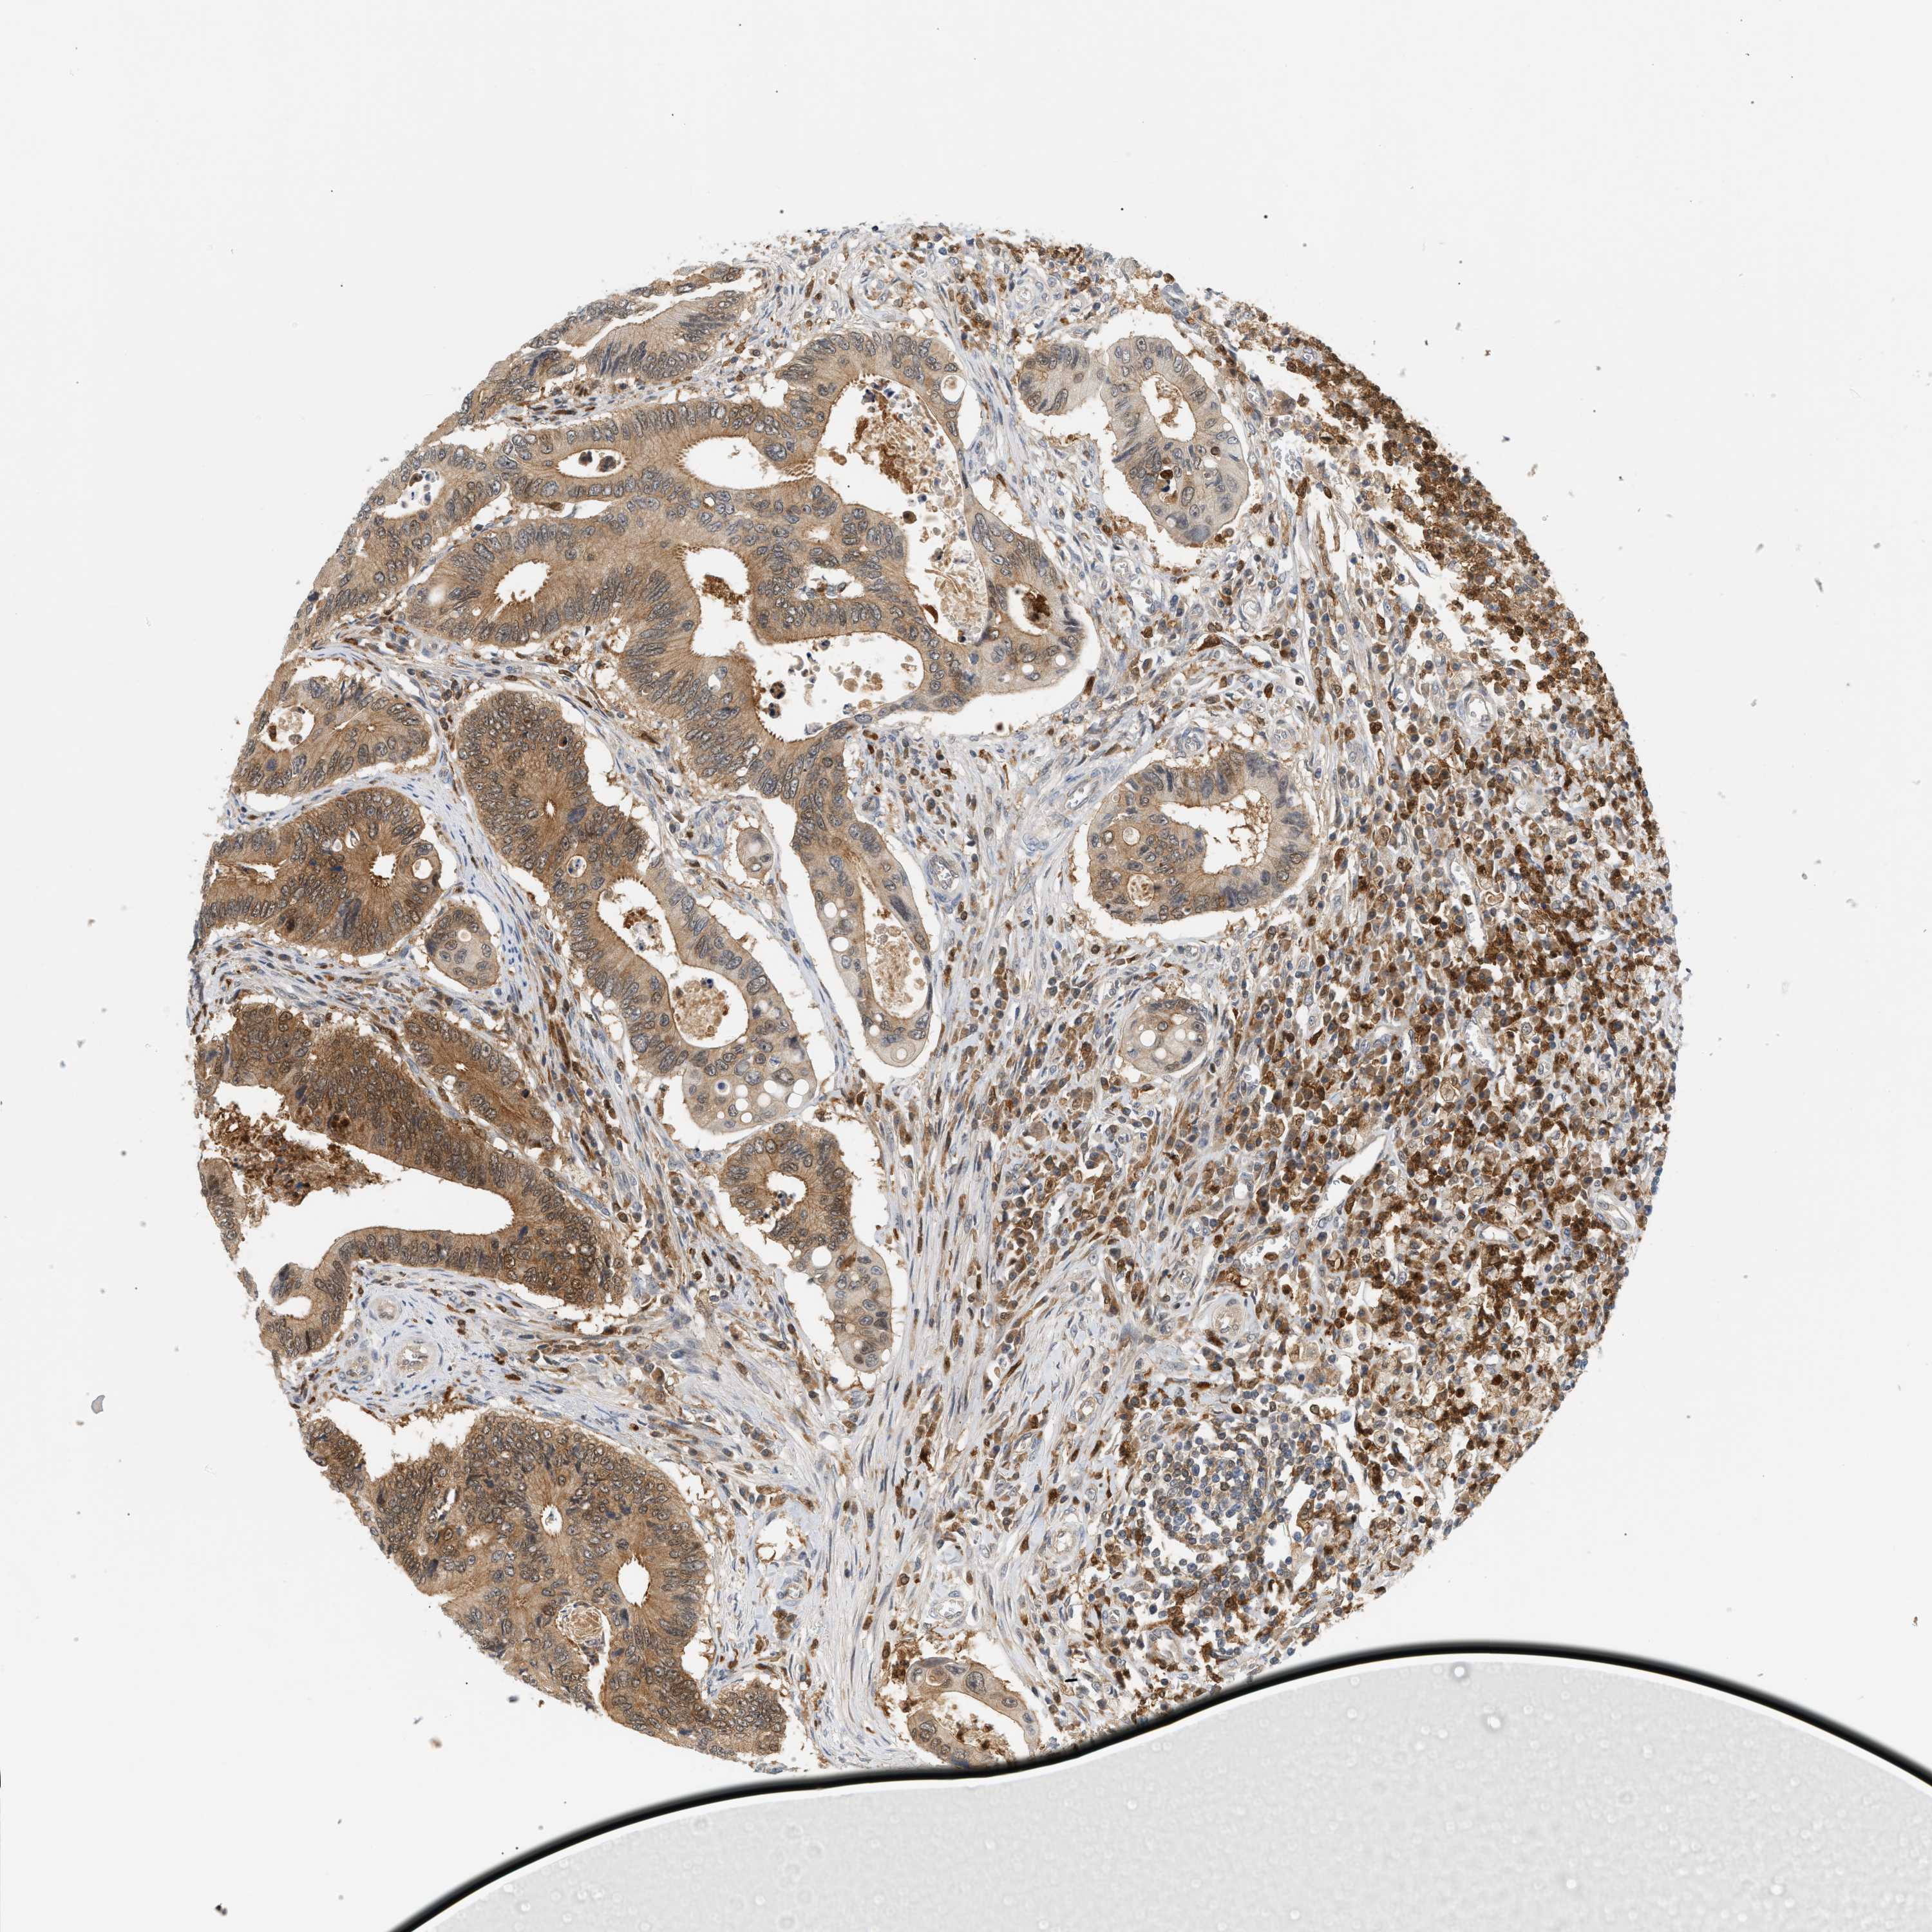

CANCER COLORECTAL CANCER Show tissue menu

Colorectal cancer

Human cancer